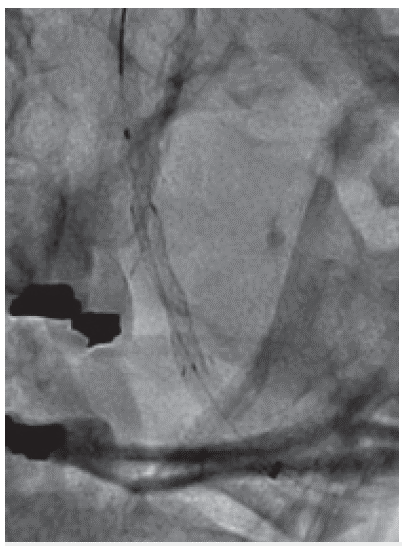

Ascenso de microcateter asistido con microguía hidrofilica para la liberación controlada de stent coronario medicado

Figura 2: Ascenso de microcateter asistido con microguía hidrofilica para la liberación controlada de stent coronario medicado